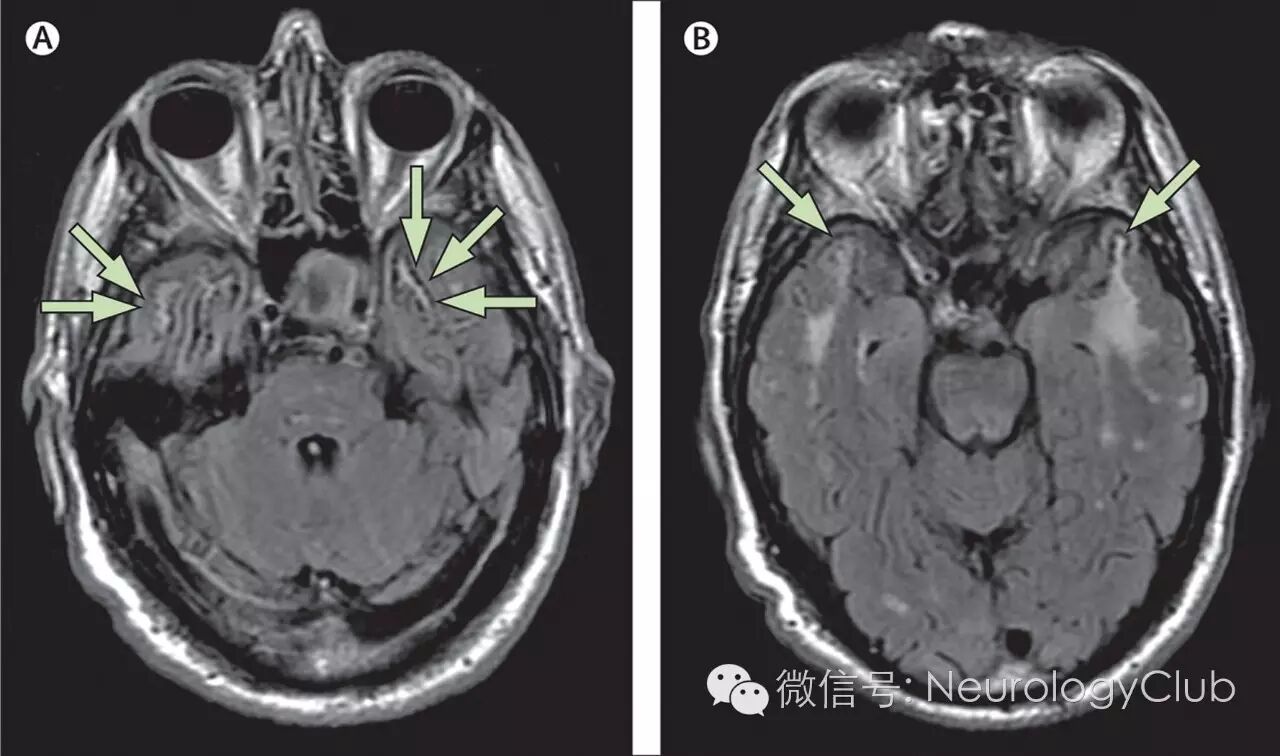

CADASIL患者在临床症状出现前即可有影像学上的改变。多对称分布,在MRI的T2像表现为大小不一的高信号,不累及弓状纤维。主要位于侧脑室周围和深部白质。以额叶白质最常受累,其次为颞叶和顶叶,而枕叶受损程度相对较轻。其中,外囊、颞极的对称性异常信号对诊断有高度提示作用。胼胝体亦可全层受累,引起胼胝体萎缩。皮层一般不受累。

疾病早期出现血管周围间隙加大,继而出现对称性孤立的单个结节状高信号区,此阶段容易与多发性硬化混淆。这些白质异常信号可以进一步扩大表现为外囊和颞极的高信号,对于年龄在20-30岁的亚临床患者,其颞极白质以及侧脑室周围出现帽状异常信号是其最早期的改变。随着病程进展双侧半球白质内大片长T2信号区相互融合,晚期小脑和脑干也受累及,约半数患者出现脑干长T2信号,其中脑桥(100%)比中脑(68%)和延髓(35%)更易受累,这一现象与年龄增长相关,出现双侧脑干病灶的CDADASIL患者可能预后不良。

颞极白质T2/FLAIR呈高信号是CADASIL的特征性表现,也称为O’Sullivan征,在 皮质下动脉硬化性脑病中无此现象,对本病的诊断敏感度为89%,特异度为86%。但O’Sullivan征对中国人CADASIL诊断并不是敏感指标。

外囊受累是CADASIL的另一特异征象,表现为T2/FLAIR高信号,诊断CADASIL的敏感度和特异度分别为93%和45%,并有助于CADASIL与其他小动脉疾病的鉴别诊断。本病也可累及基底节区内囊前肢额桥束,如外囊钩状纤维束和内囊前肢同时受累,在T2/FLAIR横轴位图像高信号呈“人”字征(Herringbone pattern)。

2腔隙性脑梗死

可广泛存在于大脑皮层下白质、基底节、丘脑、外囊、胼胝体和脑干等部位。腔隙性脑梗死在基底节的出现率高达100%,但出现在胼胝体和外囊等特殊部位的梗死灶更具有诊断价值。

(图3:T2WI可见CADASIL特征性的颞极高信号和外囊受累)

(图4:MRI上可见颞极、脑室旁和深部白质病变)

(图5:A:T1WI可见脑室旁低信号病灶;B-C:FLAIR可见脑室旁高信号病灶,外囊受累,基底节区可见腔隙性梗死)

(图9:A:颞极高信号病变;B:皮质下、外囊高信号病变;C-D:两例患者均有胼胝体受累[箭头])